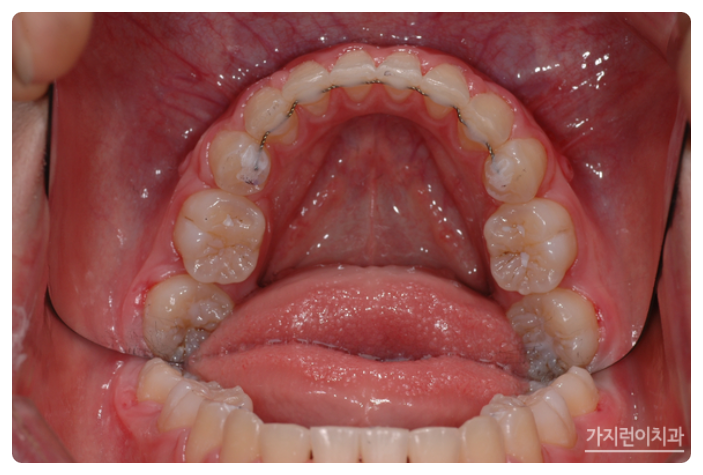

서울가지런이치과교정과 의원을 찾아주신 환자분의 모습인데요. 상악 돌출이 꽤나 심한 것을 볼 수 있습니다. 이런 경우에는 입술을 다무는 것이 어려운 정도였는데요. 전체적으로 치아를 후방으로 이동할 필요가 있어 돌출입 교정과 거미스마일 교정을 진행하게 되었습니다.

서울가지런이치과 교정과 의원, 강남에서도 거미스마일과 돌출입 치아교정이 이루어지고 있었는데요. 충분한 치아이동 공간을 확보하기 위해 상하악 1소구치를 발치한 후에 상악 잇몸뼈에 미니스크류를 식립해 효과적으로 힘을 주어 치아를 이동시켰습니다. 미니스크류를 진행하게 되면 상악 전치의 후방 이동이 일어나면서 상악 전치를 위로 합입시킬 수 있는데요. 상악이 어느 정도 이동한 것을 확인한 후에 하악에도 미니스크류를 식립해 상하악 전치를 동시에 후방으로 이동시킬 수 있었습니다.